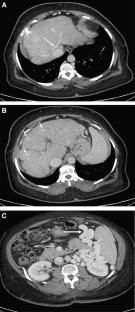

Fig. 2